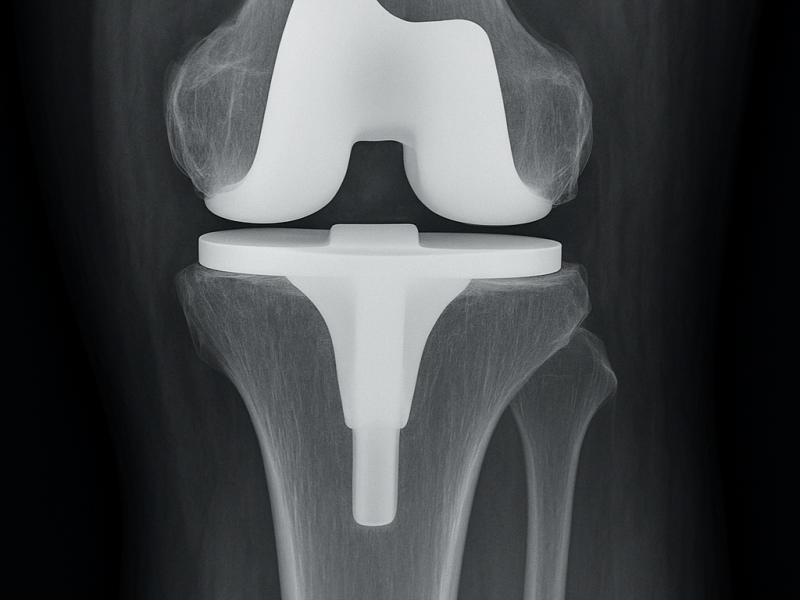

Il ginocchio è una delle articolazioni più sollecitate del corpo. Quando artrosi o traumi compromettono gravemente la sua funzionalità, il dolore può diventare costante e limitare significativamente la mobilità.

La protesi totale di ginocchio è un intervento altamente efficace per eliminare il dolore e ripristinare il corretto movimento dell’articolazione.

Tecniche Chirurgiche Moderne

L’intervento prevede la sostituzione delle superfici articolari danneggiate con componenti protesiche progettate per garantire:

Allineamento preciso dell’articolazione

Stabilità del ginocchio

Movimento naturale e fluido

Durata nel tempo dell’impianto

Pianificazione Personalizzata

Ogni intervento viene studiato sulla base dell’anatomia del paziente e del grado di degenerazione articolare.

Questo consente di ottenere risultati funzionali ottimali e una maggiore soddisfazione del paziente.

Recupero Post-Operatorio

Il percorso riabilitativo è fondamentale per il successo dell’intervento:

Mobilizzazione precoce

Progressivo recupero della forza muscolare

Ritorno graduale alle normali attività quotidiane